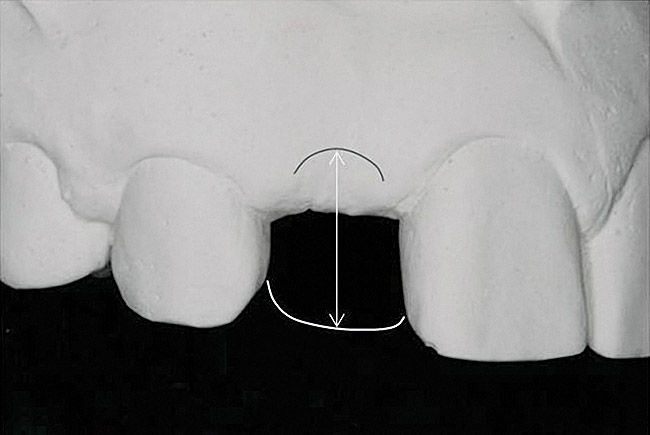

Figure 2 Identification of sufficient inter-radicular space: The radiographic representation of inter-radicular space (Fig 2) reveals abundant space for a single-tooth implant; at the alveolar crest,

> 6 mm of interproximal space is available for placeme

Figure 2

Figure 3 Identification of sufficient inter-radicular space: The radiographic representation of inter-radicular space (Fig 2) reveals abundant space for a single-tooth implant; at the alveolar crest,

Figure 3